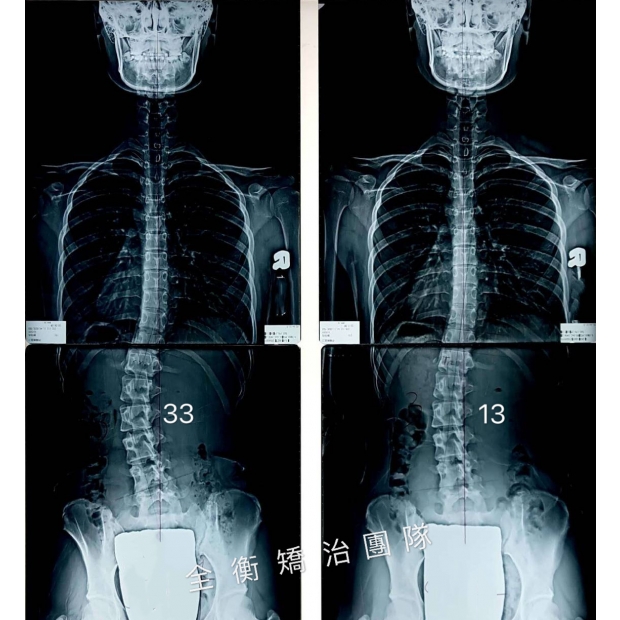

17歲中度側彎男生,積極矯治4個月,度數降低一半17歲中度側彎男生,積極矯治4個月,度數降低一半

17歲,骨齡3,腰彎22度男生,經過4個積極矯治:穿背架+復健運動

度數從22度改善至10度,減少了55% -